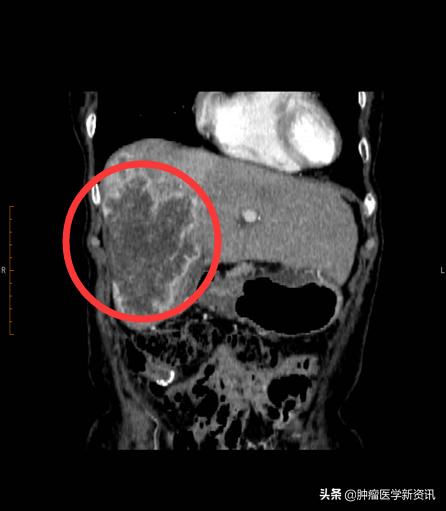

治疗前

2020年3月,王女士母亲在持续进行2次iNKT癌症免疫治疗+肝部介入后,2个月的时间,王女士的母亲肝部10cm肿瘤缩小了1/3,肿瘤标志物下降接近一半,精神也越来越好,就连吃饭都比之前好多了,可以如正常人般生活了。